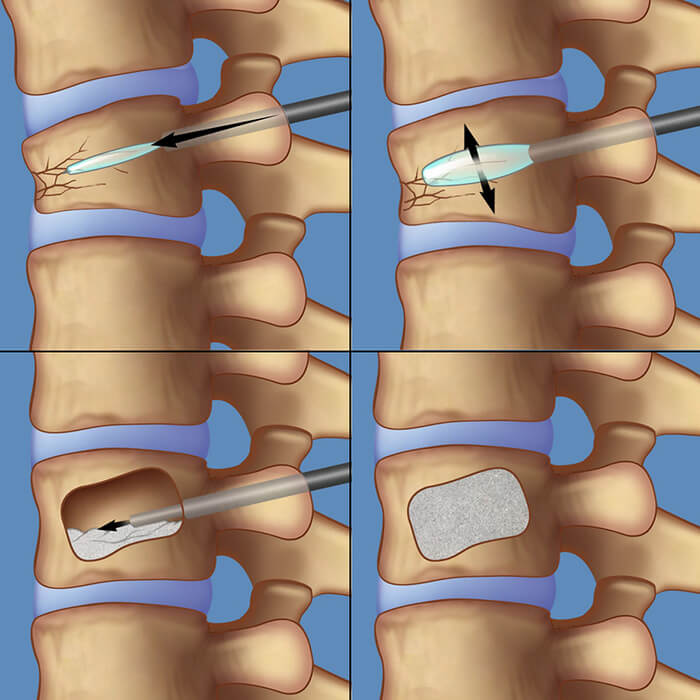

Η κυφοπλαστική είναι η πλέον σύγχρονη μέθοδος αντιμετώπισης των οστεοπορωτικών καταγμάτων της σπονδυλικής στήλης. Κατά την επέμβαση, ο ορθοπαιδικός χειρουργός, με ακτινοσκοπική καθοδήγηση, εισάγει διαδερμικά (με δύο μικρές τρυπούλες) στον σπόνδυλο μια μικρή συσκευή σαν μπαλονάκι, το οποίο φουσκώνει και αποκαθιστά τον σπόνδυλο, επαναφέροντάς τον στο αρχικό του σχήμα και θέση. Έπειτα, ξεφουσκώνει το μπαλονάκι και γεμίζει το κενό που έχει δημιουργηθεί με ειδικό οστικό τσιμέντο, σταθεροποιώντας τον σπόνδυλο.

Για κάθε σπόνδυλο απαιτούνται περίπου 30 λεπτά, η επέμβαση γίνεται με τοπική αναισθησία ή ήπια καταστολή (μέθη), είναι εντελώς αναίμακτη και ο ασθενής μπορεί μετά από λίγες ώρες να επιστρέψει στο σπίτι του και στις καθημερινές του δραστηριότητες.